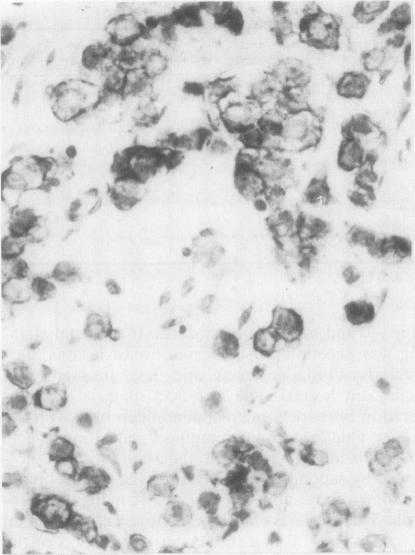

An evaluation of Ca 1 antibody staining was performed on paraffin sections from 136 breast lesions (64 benign and 72 malignant). Although cytoplasmic staining was encountered significantly more often in malignant lesions, the false negative rate was 6.9% and the false positive rate 56.2%. Benign lesions which showed positive staining included gynaecomastia, cystic mastopathy and fibroadenomata. Various other monoclonal antibodies showed staining similar to Ca 1 antibody. Ca 1 antibody was observed to bind to epithelial membrane antigen-coated sepharose beads.